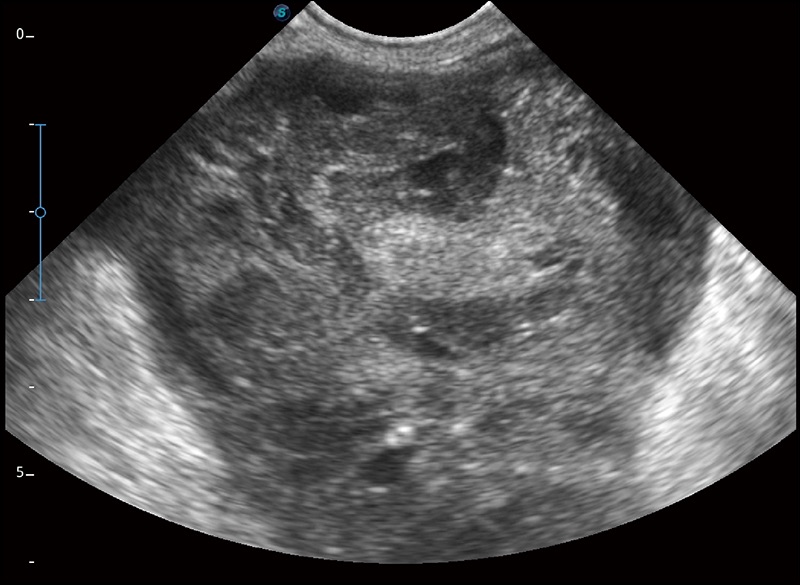

α1卓越的图像质量和便捷的工作流程,使每位宠物医生都能轻松扫查。其全面的兽用应用功能和紧凑型的结构设计,可以满足动物检查的多种需要。专业的预设检查模式和多领域测量软件包有助于为不同类型的动物提供检查, 让宠物医生能够出色的完成工作。

在不牺牲时间分辨率的情况下提供出色的图像

空间复合成像

优化不同角度的图像

为心脏功能评估提供更多诊断信息